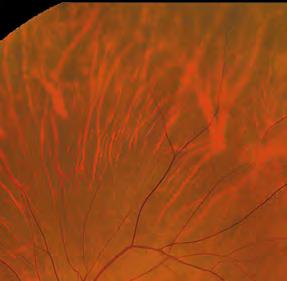

Dry eye patients at Park Vison have pre-treatment diagnostic measurements taken, including tear interferometry, tear film break-up time (TBUT), tear meniscus height (TMH), meibography, digital slit lamp images, fluorescein staining and a questionnaire on symptoms. This is not only important for clinical decision-making, but for patients to be able to see improvements.

Medmont Meridia TBUT and meibography